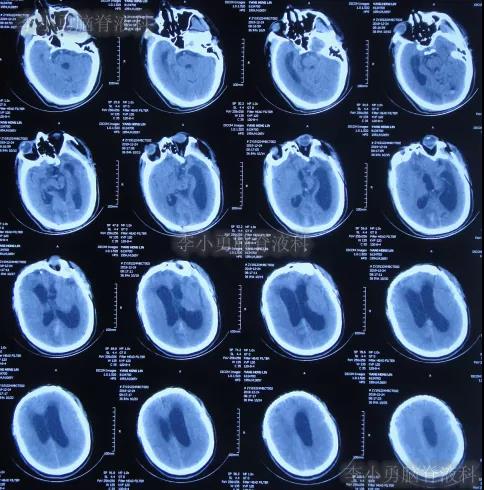

2019年10月20日患者骑电动车在马路上行驶时被大货车撞倒,当时意识清楚,只感到有些头晕,未在意就自行回家,但回家后约3-4小时出现头晕加重,并伴有恶心呕吐的症状,家人急送到当地的河北省邯郸市某医院,查头颅CT示脑出血(图-1);既往病史2015年曾因头部外伤致硬膜下血肿,进行了钻孔引流术。

图-1:2019年10月20日头颅CT

急诊进行了开颅去骨瓣血肿清除术,术后次日查头颅CT示去骨瓣术后(图-2)。

图-2:2019年10月21日头颅CT